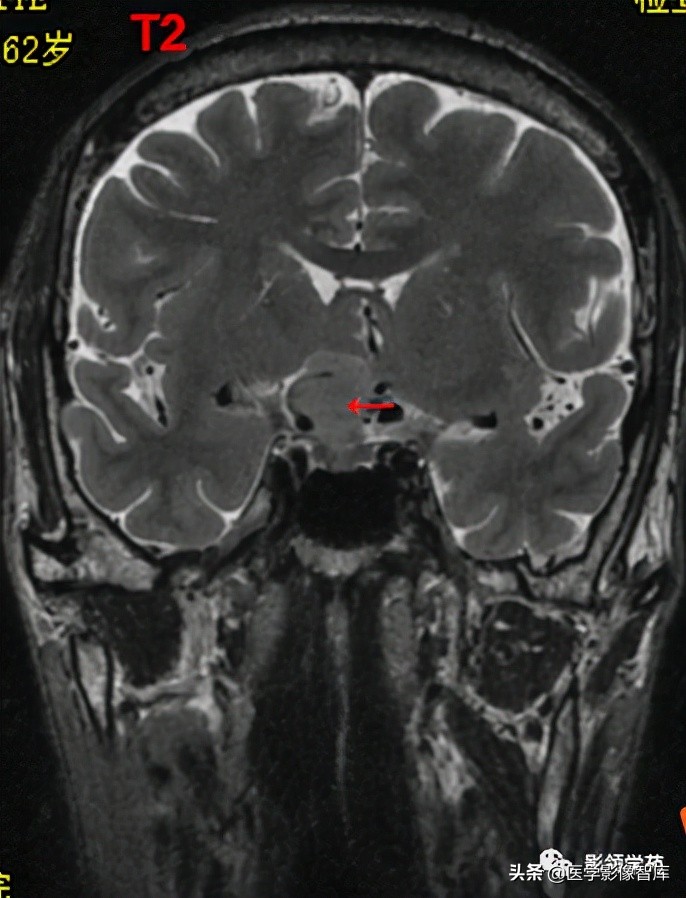

男 62岁,右眼视朦半年

鞍区见一类圆形稍高密度肿块影,密度较均匀,边界较清,位置稍偏右,向上突入鞍上池内,周围骨质未见破坏。

前颅窝底、鞍前区见一肿块影,呈等T1等T2信号,信号均匀,边缘清楚,以宽基底与颅底接触。

病灶呈均匀明显强化(馒头样),见脑膜尾征;肿块后缘部分进入鞍内,挤压垂体前方和视交叉,垂体柄显示不清楚。

右侧大脑前动脉A1段完全被肿瘤包绕;左侧大脑前动脉A1段与肿瘤分界不清,但无明显包绕和推移。双侧海绵窦未见异常征象。